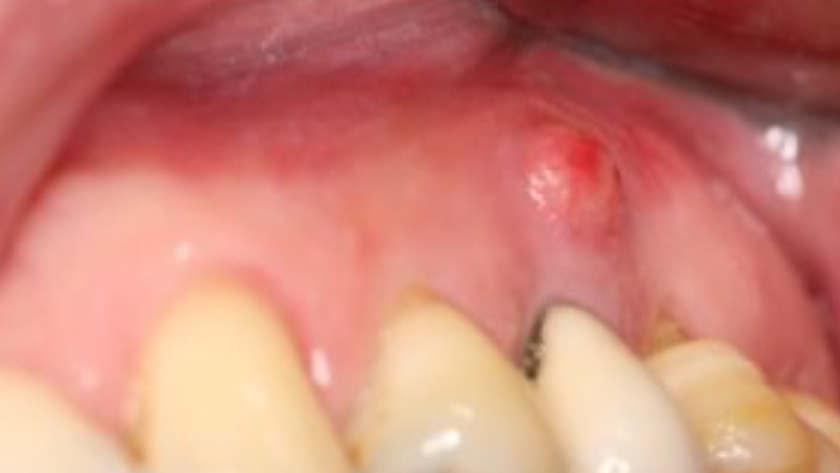

Tooth 13* required extraction in a 54-year-old male patient. The buccal bone was absent. Goal was to restore the site with an implant.